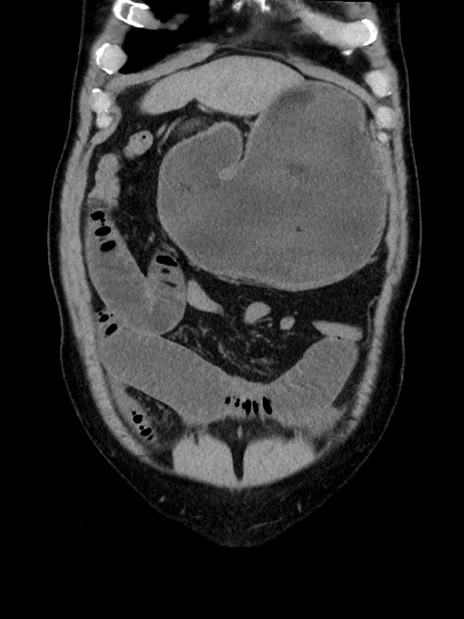

症例35(冠状断像)

【症例】70歳代 男性

【主訴】腹部膨満、嘔吐

【現病歴】昨日より腹部膨満感出現。本日増悪し、仙痛出現。嘔吐あり、受診。

【既往歴】糖尿病、胆摘後

【身体所見】BP 149/80mmHg、HR 74/min、BT 35.9℃、腹部:膨満、軟、圧痛なし。腸雑音減弱あり。上腹部正中切開瘢痕あり。

【データ】WBC 13500、CRP 1.72